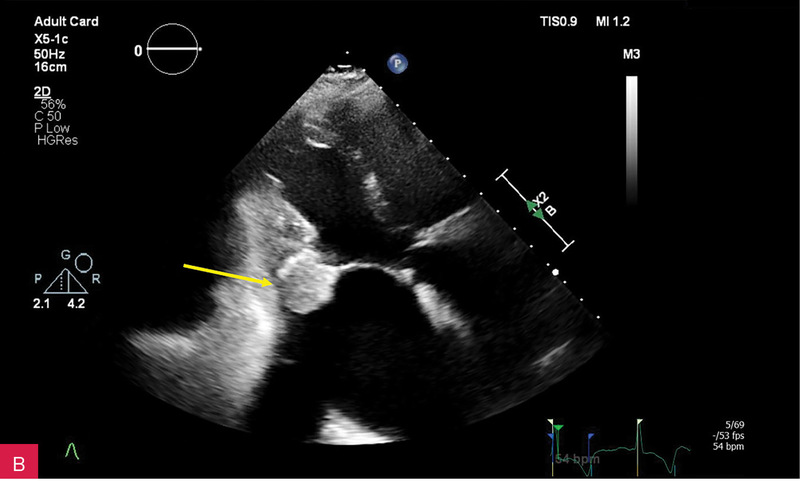

Rycina 3A-C. Badanie echokardiograficzne przezklatkowe (TTE) w osi krótkiej przymostkowej na różnych poziomach – płatków zastawki mitralnej (A), strun ścięgnistych (B) i mięśni brodawkowatych (C) – obrazuje owalną zmianę guzowatą, o dużych rozmiarach i nierównej echogeniczności, z widocznym wzmocnieniem brzeżnym